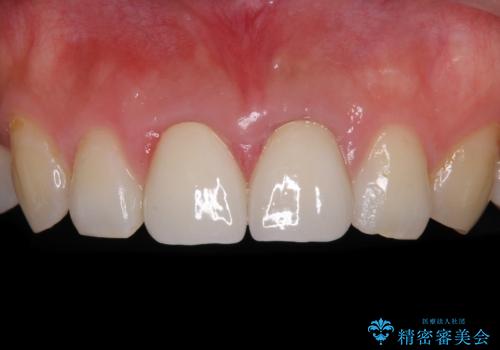

海外勤務中のインビザラインによる矯正治療

- 前歯のクロスバイトを気にして来院され患者様です。

定期的に日本には帰国するものの、日ごろは海外でお仕事をされているとのことで、インビザラインによる治療を希望されました。

トラブルが起こった時に対応ができない、来院を帰国のタイミングに合わせなければならないため治療が長期化するなど困難はありますが、ワイヤー矯正と比べると治療を進めやすいといったメリットがあるので、インビザラインにて矯正治療を行うこととしました。

治療期間が世界的な感染症の流行時期と重なったため、海外と日本での往来が困難となり、治療継続が懸念されました。

それでも、しっかりとマウスピースを装着してくださったので、大きなトラブルもなく治療を終えることができました。